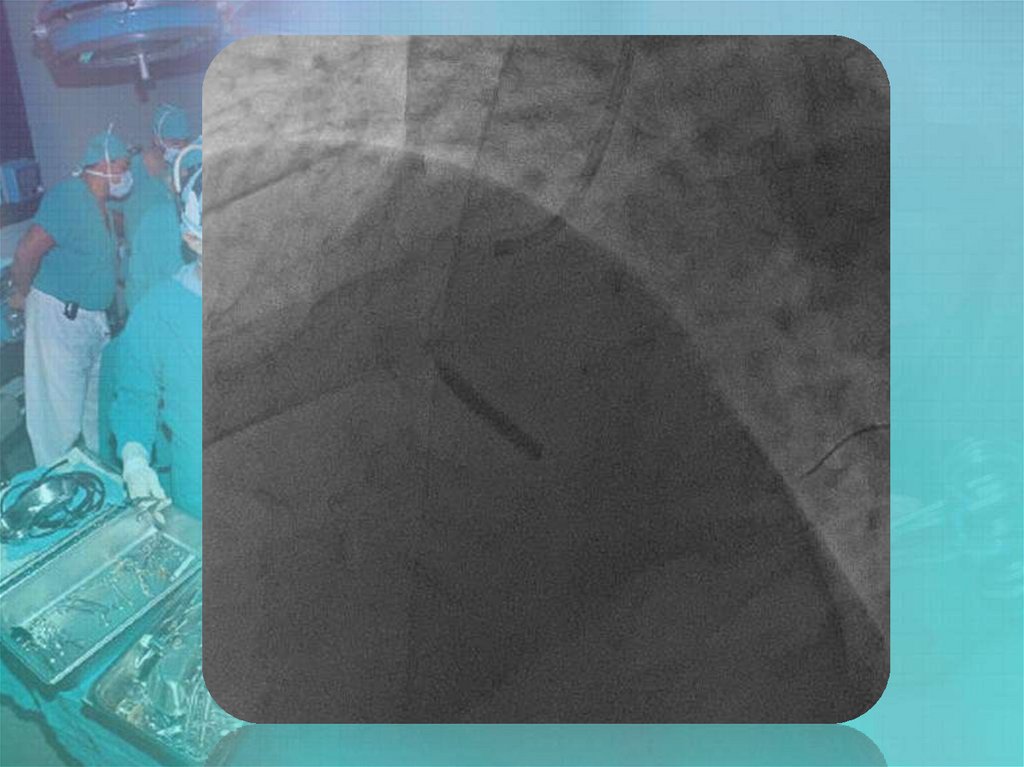

Коронары. СНК кафедры факультетской хирургии №2 лечебного факультета